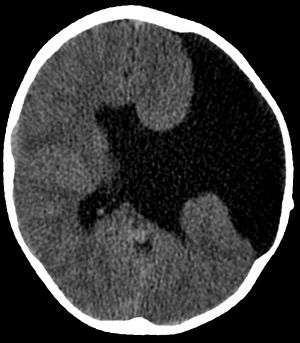

Axial CT scan showing schizencephaly in a 6-year old child

Schizencephaly (from Greek skhizein, meaning "to split", and enkephalos, meaning "brain")[1][2] is a rare birth defect characterized by abnormal clefts lined with grey matter that form the ependyma of the cerebral ventricles to the pia mater. These clefts can occur bilaterally or unilaterally. Common clinical features of this malformation include epilepsy, motor deficits, and psychomotor retardation.[3]